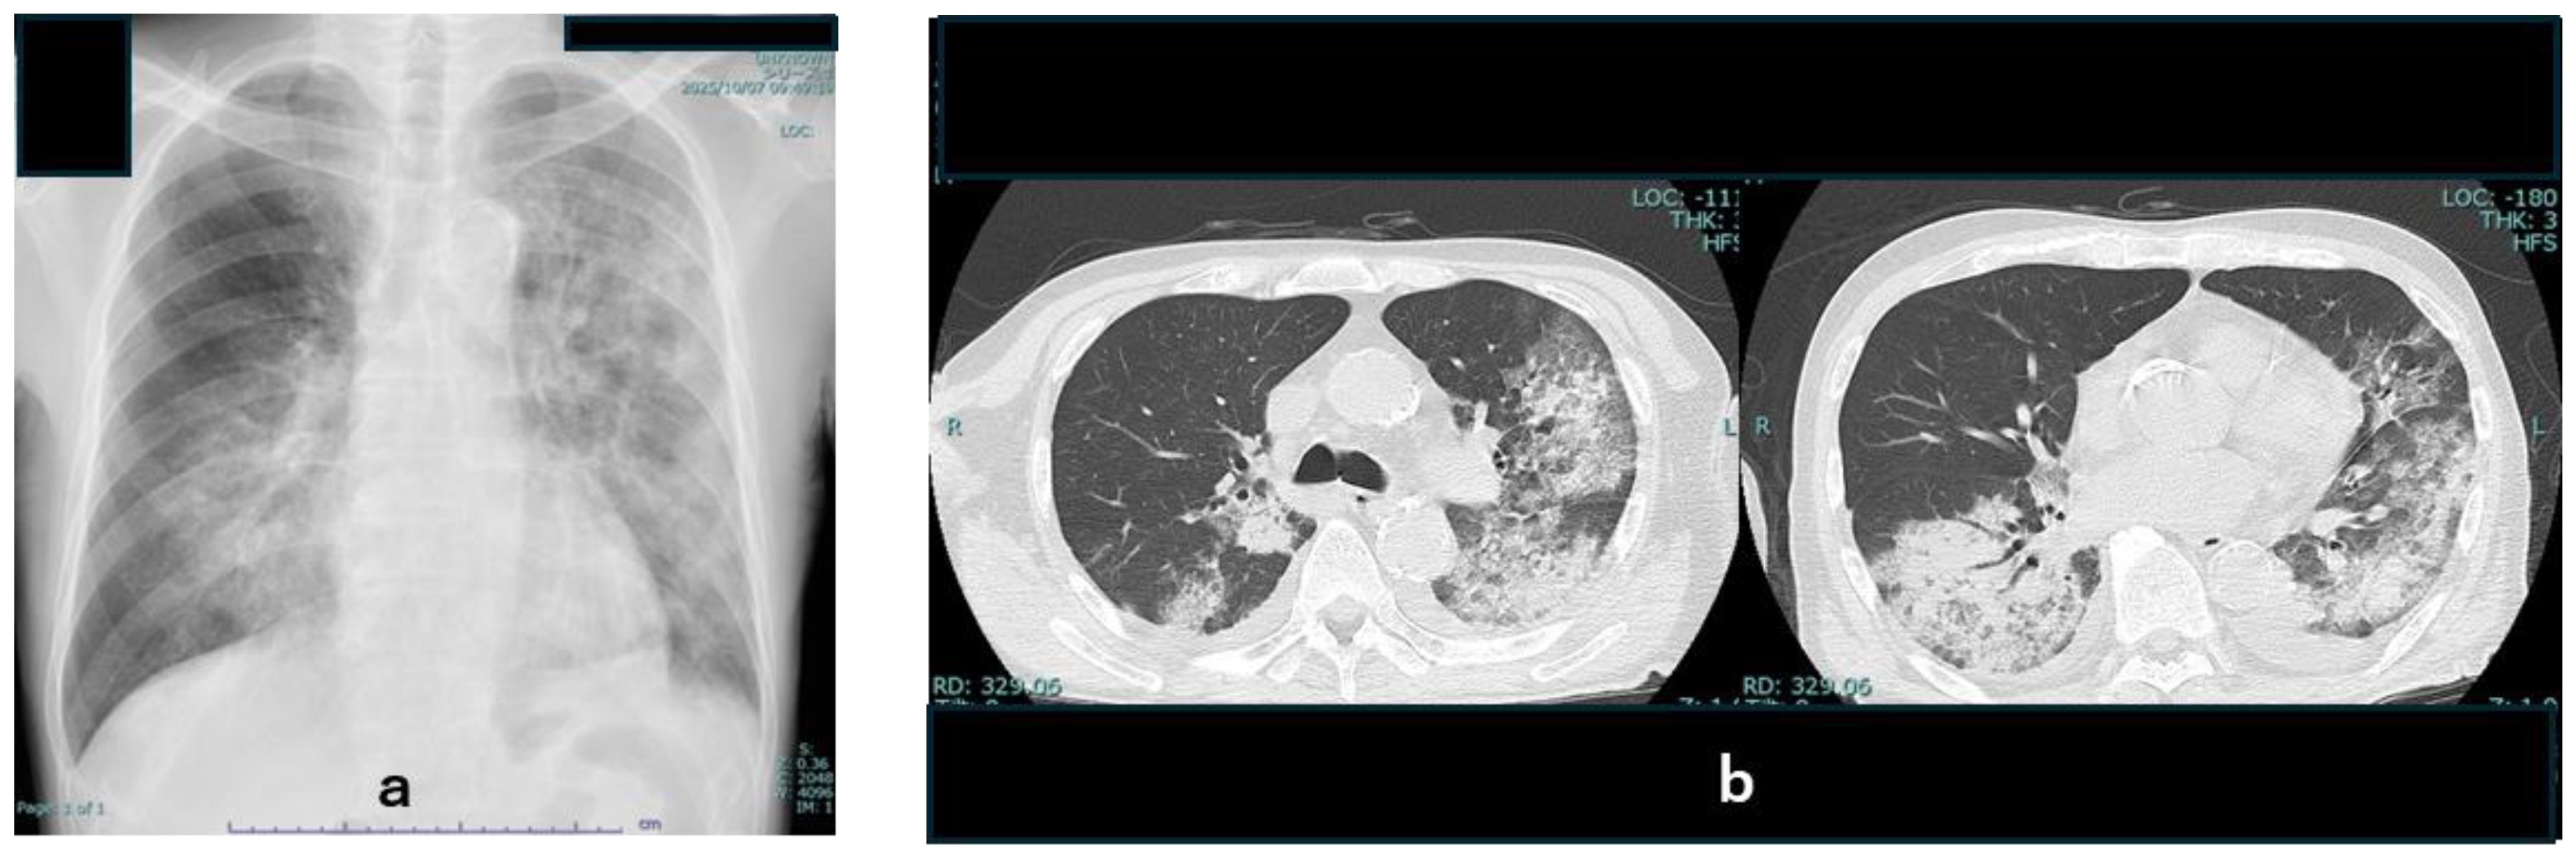

2.4. Laboratory and Imaging Findings

3. Clinical Course and Management (Figure 2)